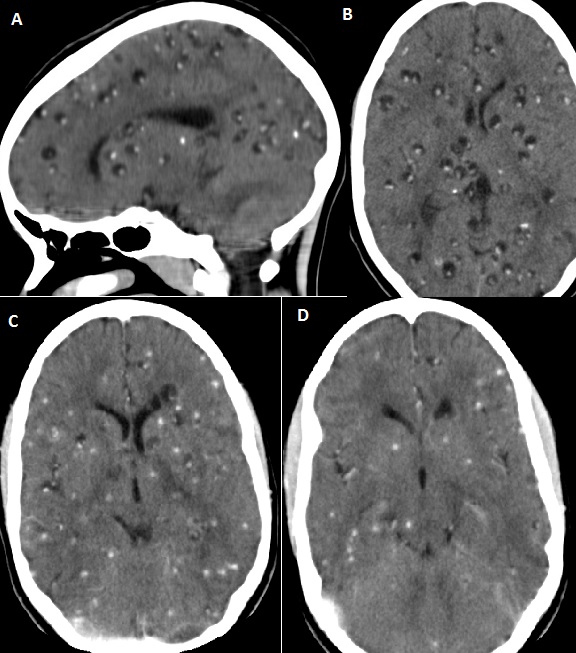

13-year old girl presented to the medical outpatient department with epilepsy diagnosed within the preceding 3 months. However, her seizures were becoming more frequent despite being on Carbamazepine and Phenobarbital at maximal tolerable dosages. She had no recent history of head trauma neither any other medical illness. Her physical examination was unremarkable. Her full blood count, liver and kidney function tests were within normal limits. A Brain CT scan was ordered which revealed multiple calcified and vesicular cysts within the Brain parenchyma; features consistent with Neurocysticercosis. The stool examination was negative for Taenia species ova. She was treated with Albendazole 400mg tid for 1 month and subsequent CT scans at 4 weekly intervals showed marked reduction in the number of active (vesicular cysts). Brain CT scans showing multiple vesicular cysts before treatment with Albendazole (A and B) and after treatment (C and D)